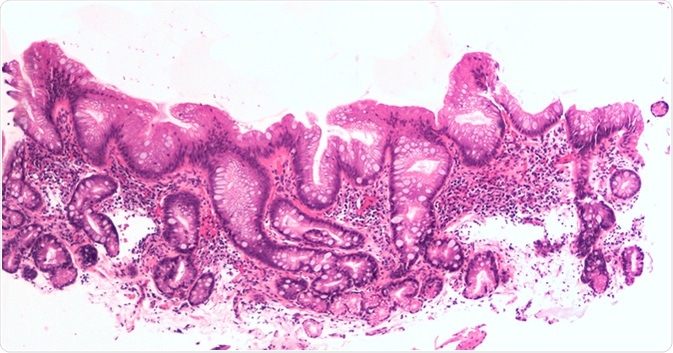

Intestinal metaplasia of the esophagus, aka Barrett

Intestinal metaplasia of the esophagus, aka Barrett's, is a response to injury due to acid reflux. Image Credit: David Litman / Shutterstock